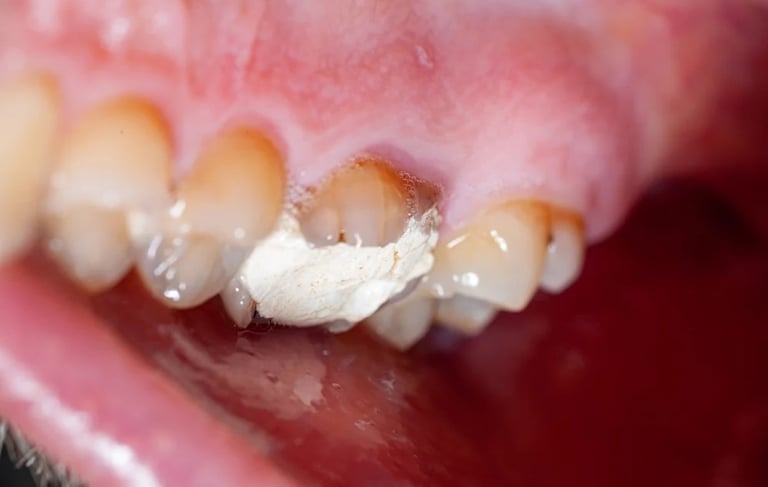

Se revisa si hay fracturas en la parte visible del diente. Las fracturas de la corona pueden ser causadas por trauma o caries extensas y pueden afectar el tratamiento endodóntico.

Evaluación de fracturas de la corona